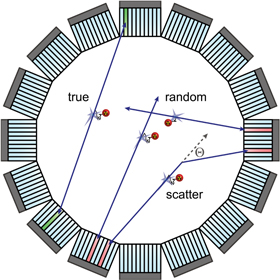

The positrons emitted by PET radiotracers almost immediately annihilate with electrons in the human body, resulting in the back-to-back emission of pairs of 511 keV annihilation photons. A PET scanner essentially consist of a ring of scintillation detectors, as indicated schematically in figure 1. Each detector contains an array of scintillation crystals. The crystal pitch is in the order of a few mm and determines the system spatial resolution, while the thickness of the crystal layer must be a few cm to ensure high detection efficiency. Multiple detector rings are stacked coaxially to obtain a cylindrical detector geometry with high angular coverage of the field-of-view (FOV). When a crystal absorbs an annihilation photon, it converts its energy into a small flash of light, typically containing in the order of ∼104 visible and/or ultraviolet photons. The duration of this scintillation pulse typically is in the order of 101–102 ns. Photosensors coupled to the backside of the crystals convert these tiny flashes of light into electronic signals. When two gamma quanta of the correct energy are detected in coincidence, i.e. within a time window of a few ns, it is assumed that the annihilation has occurred on the line connecting the two fired crystals, the so-called line-of-response (LOR). The event is called a 'true' coincidence if the two photons are indeed the result of the same annihilation event (figure 1). After collecting a large number (107–108) of LORs, one can reconstruct a tomographic image of the biomarker distribution within the subject (Defrise and Gullberg 2006, Qi and Leahy 2006).

Figure 1. Schematic representation of a PET ring consisting of 16 detector modules. Also indicated are three types of coincident event: true, random, and scattered. See text for detailed explanation. Reproduced with permission from Seifert (2012).

Standard image High-resolution imagePET image quality is affected by various sources of error (Cherry 2006, Lewellen 2008, Peng and Levin 2010). For example, the system intrinsic spatial resolution is determined by the finite range of the positrons (typically <1 mm), the accolinearity of the annihilation quanta (<0.5°), the finite crystal pitch (typically <5 mm), and parallax effects in case the depth of interaction (DOI) in the crystal is unknown and the annihilation occurs off-center (such as the true event in figure 1). The image signal-to-noise ratio (SNR) is determined for a large part by counting statistics and, consequently, is limited by the radiotracer dose, the scan time, and the system sensitivity. The first two factors should be kept as small as possible, so it is imperative to maximize sensitivity.

In addition to counting statistics, the image SNR is affected by so-called 'randoms,' i.e. coincidences that do not originate from the same annihilation event, and 'scatters,' i.e. events in which at least one of the annihilation photons has scattered within the patient before being detected (figure 1). Clinical PET images are commonly corrected for randoms and scatters, but the statistical fluctuations in these contributions nevertheless worsen the image SNR. In fact, also the reconstructed spatial resolution of clinical PET images is often limited by the SNR rather than the system intrinsic spatial resolution. Thus, the importance of high sensitivity is hard to overestimate.